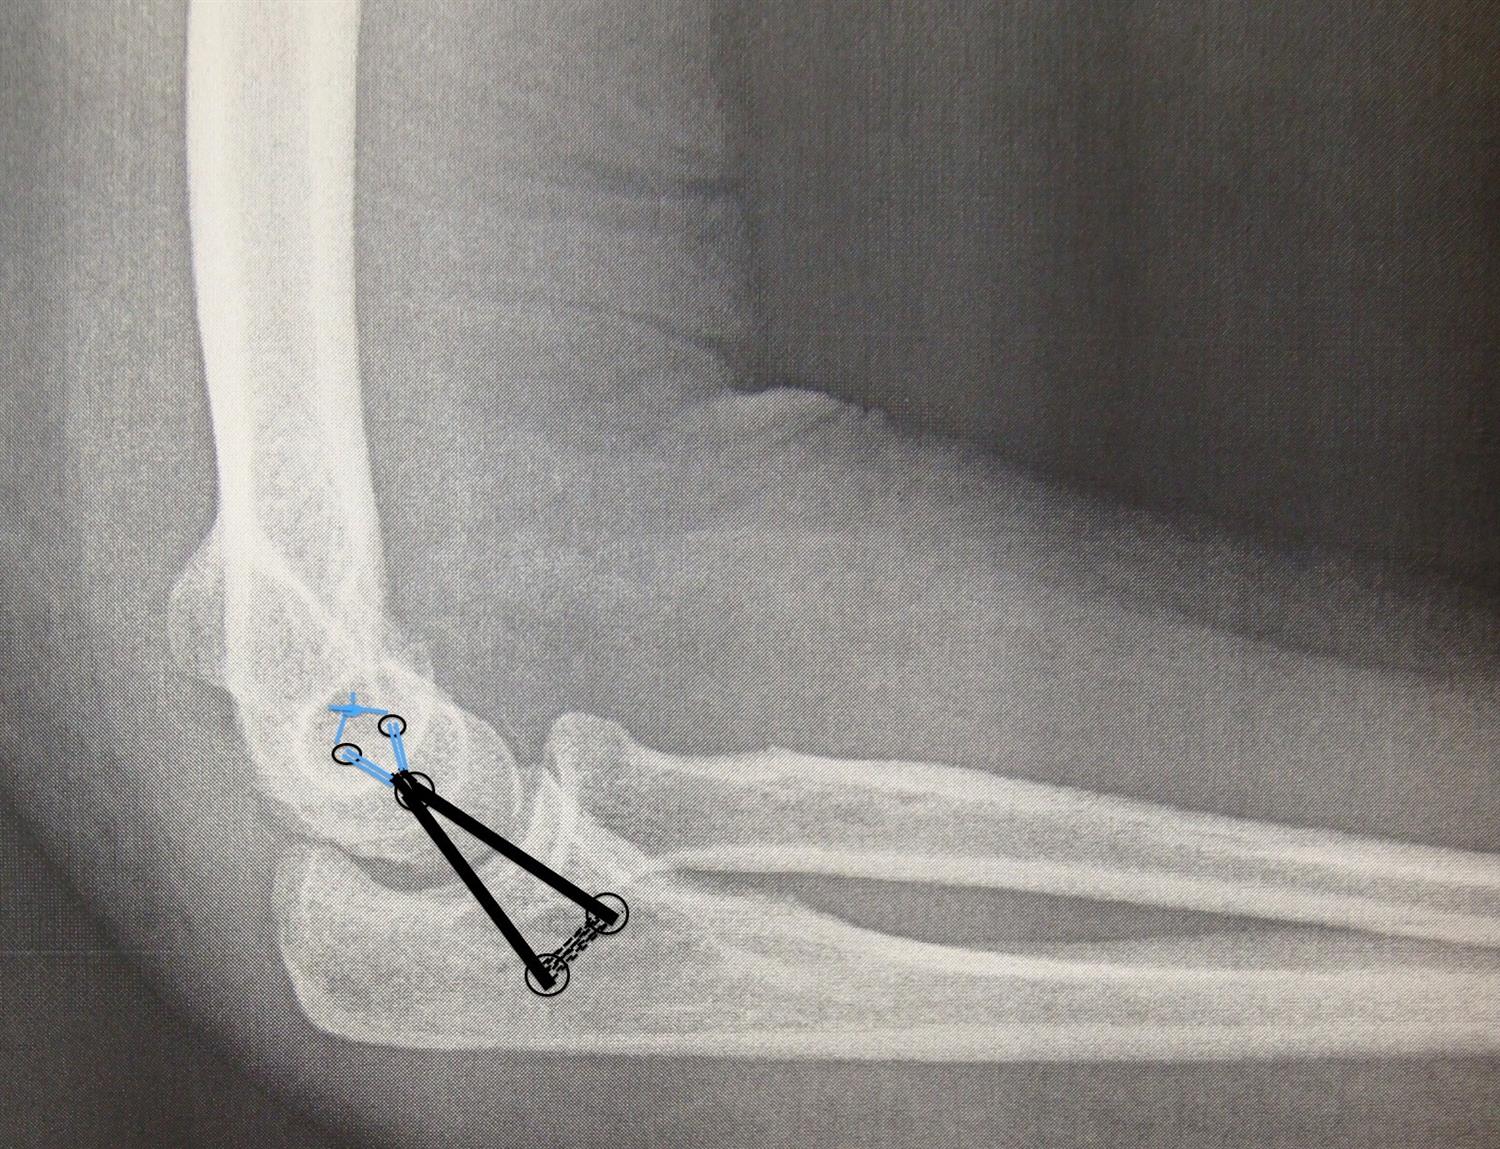

From pubs.rsna.org

Elbow Imaging in Sport Sports Imaging Series Radiology Ulnar Collateral Ligament Elbow Physical Therapy Exercises rehabilitation guidelines for ulnar collateral ligament reconstruction (palmaris longus graft, gracilis graft) this protocol is. rehabilitation protocol for ulnar collateral ligament reconstruction (palmaris longus graft, gracilis graft) phase i: ulnar collateral ligament injuries generally occur when repetitive stress damages the inside of the elbow, compromising. in this phase, controlled passive elbow and forearm rom exercises are. Ulnar Collateral Ligament Elbow Physical Therapy Exercises.